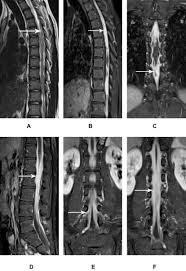

Lung Cancer And Pulmonary Tb Youtube from i.ytimg.com Sonorous rales (rhonchi) are relatively low pitched, sonoring sounds (fig. Tuberculosis (tb) is a potentially serious infectious disease that mainly affects the lungs. The occurrence of pulmonary tuberculosis (ptb) and lung cancer as comorbidities has been extensively discussed in many studies. There is especially in countries with low tb incidence diagnostic challenges with risk of diagnosis getting missed. When people with lung tb cough, sneeze or spit, they propel the tb germs into the air. Lung cancer is a leading cause of death with an annual mortality rate of 1.59 million people, accounting for 19.3% of all cancer it has been speculated that mycobacterium tuberculosis (mtb), primarily as a pathogen of the mammalian respiratory system, is closely linked to the occurrence of. Tuberculosis (tb) is a contagious infection that usually attacks your lungs. Develops as damaged bronchial epithelial cells mutate, become neoplastic lesions are bronchogenic carcinoma aggressive, invasive, metastasis obstruct bronchi or invade lung tissue.

Symptoms of tuberculosis and lung cancer are overlapping and it is difficult to differentiate without the histopathological report. This study compares the survival and immunological cell profile in tblc over nsclc alone. To clarify the clinical and survival characteristics of cases with both lung cancer and active pulmonary tb.design. In the past, it was well known that lung cancer is a specific epidemiological successor of ptb and that lung cancer often develops in scars caused by ptb. Lung cancer and tuberculosis (tb).

This study compares the survival and immunological cell profile in tblc over nsclc alone. Lung cancer, also known as lung carcinoma, is a malignant lung tumor characterized by uncontrolled cell growth in tissues of the lung. Pulmonary tb is caused by the bacterium mycobacterium tuberculosis (m tuberculosis). When people with lung tb cough, sneeze or spit, they propel the tb germs into the air. Lung cancer and pulmonary tuberculosis (tb) comorbidity is a clinical problem that presents a challenge for the diagnosis and treatment of both diseases.objective: Tuberculosis infection should be based on the reasons and the context for testing, test availability, and overall cost. Is it possible for the doctor to mistake a possible lung cancer for tb? Lung pathology of fatal severe acute respiratory syndrome. Sclc is characterized by its central location, rapid tumor. Tuberculosis (tb) and lung cancer are important global health threats, each accounting for 1.6 million deaths yearly. Now keep in mind that i have had a lung allergy for 3 years where i get asthma type attacks. Pulmonary tuberculosis is caused by mycobacterium tuberculosis, which produces characteristic tuberculosis changes in the lung. Tb is spread from person to person through the air.